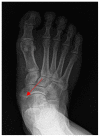

Spinal intradural hematoma (SIH) is a rare condition which can cause neurological sequelae such as permanent motor weakness and sensory loss in the lower extremities. Herein, we describe a case of SIH following spinal anesthesia. The patient was a 30-year-old man who underwent treatment for accessory navicular syndrome at our department. The patient was not receiving anticoagulation therapy, and spinal anesthesia was thus selected. No symptoms of hematoma were observed in the immediate postoperative period, but the patient complained of pain in both buttocks on postoperative day 5. However, neither motor weakness nor sensory loss were observed. Additionally, as the radiating pain extending to the lower extremities typical of neurological pain was not observed, musculoskeletal pain was suspected. Magnetic resonance imaging revealed intradural hematomas at L4-5 and S1. Conservative treatment and follow-up evaluations were performed to ensure that additional neurological sequelae did not occur. Six months after symptom onset, his pain Numeric Rating Scale score was 0, and no other neurological findings were observed. However, in patients who undergo spinal anesthesia, localized pain in the back without other neurological symptoms and lack of radiating pain may be associated with more than musculoskeletal pain. Such patients must be continuously monitored.